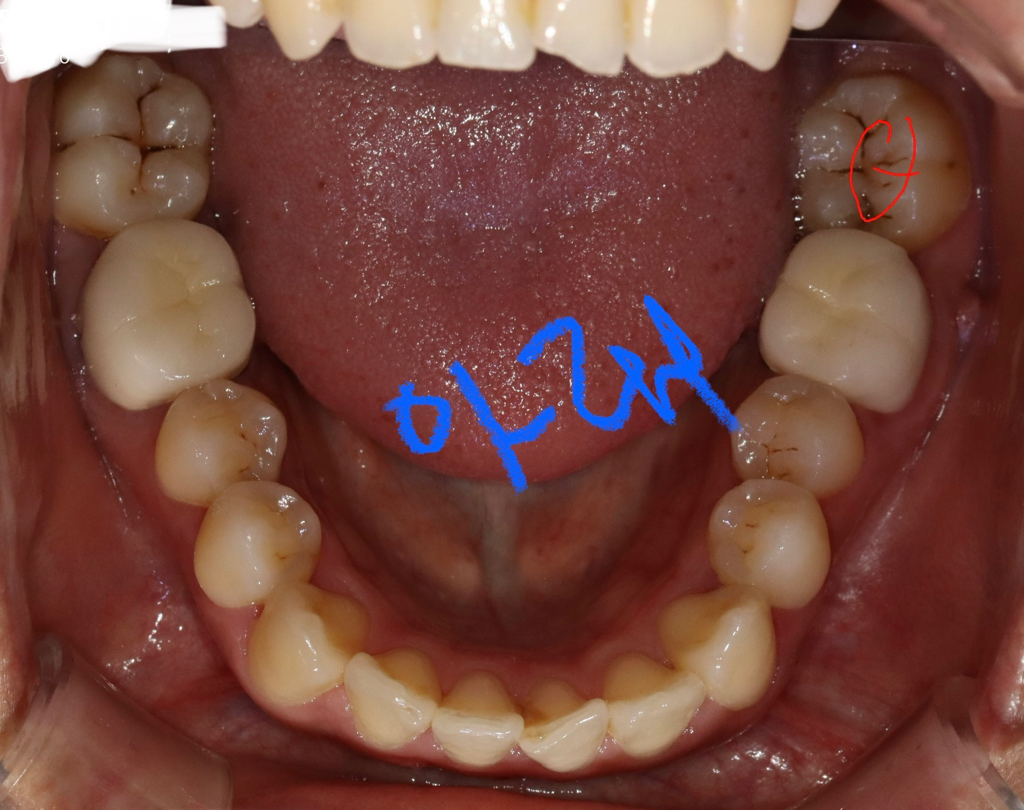

사진만 가지고는 정확한 충치 판별이 어렵습니다. 레진은 대략 10~20만원, 인레이는 30~40만원 정도 입니다.

충치 범위가 넓어서 인레이를 해야될 가능성이 높아 보입니다. 인레이 가격은 재료에 따라 다릅니다. 대략 25-40만원까지 다양합니다.

현재 사진상으로 정확한 견적을 내기는 어려우며 자세한 견적은 치과에 방문하여 상담받길 권합니다. 치과마다 금액에 차이는 있을수 있기에 2-3군데에서 견적 받아보길 권합니다.